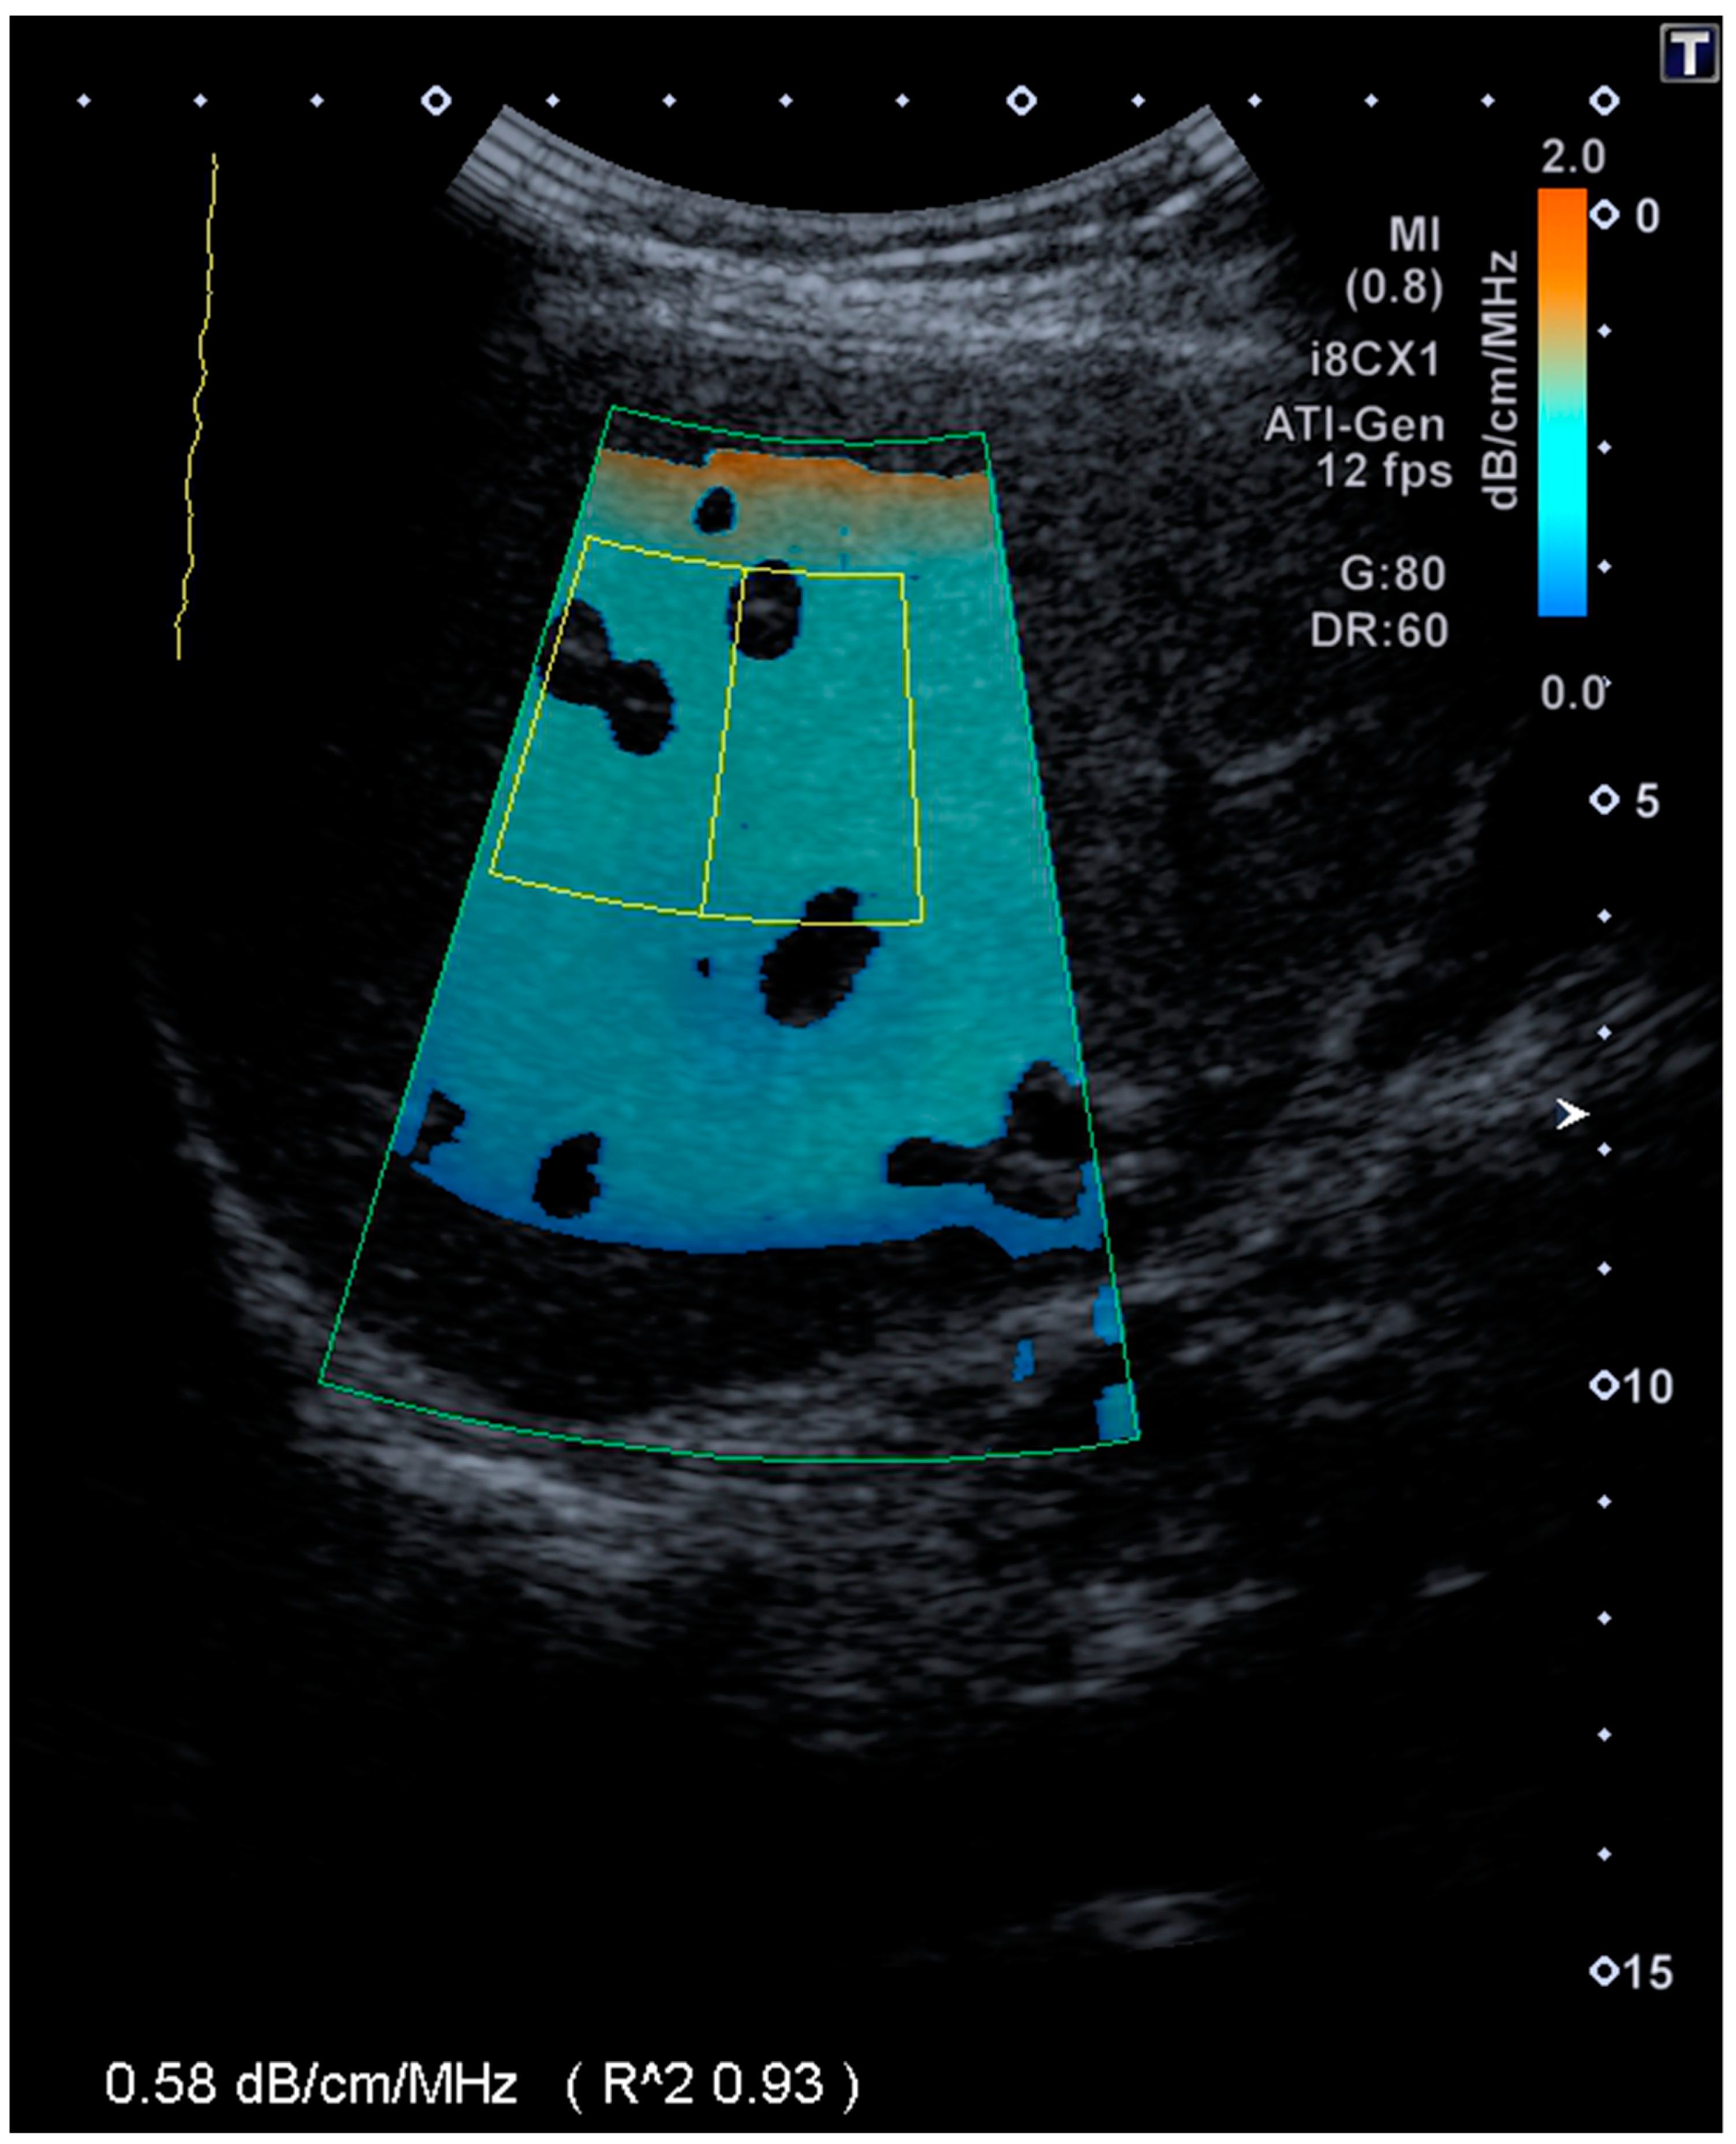

2.2. ATI

| ATI | 0.56 dB/cm/MHz, Range 0.43–0.96 dB/cm/MHz |